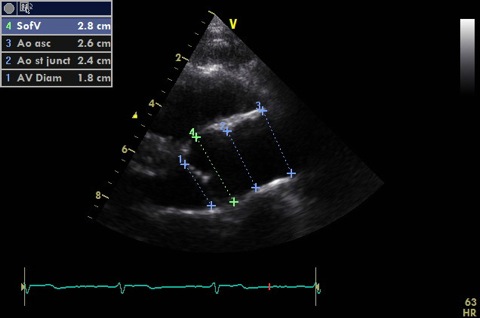

Measure in 2D:

- LVOT (up to 1 cm from aortic annulus - must PW at same point in A5C). Image should be shallow, narrow and zoomed to improve accuracy. Cross sectional area is calculated from this.

- Aortic annulus

- Sinuses of valsalva (widest bit)

- Sinotubular junction (where S of V become ascending aorta)

- Ascending aorta (include a measurement with probe tilted slightly superiorly)

- Proximal RVOT in diastole (in line with AV leaflets). Not shown

- LA end systole (in line with AV leaflets) if not measured with M-mode. Not shown